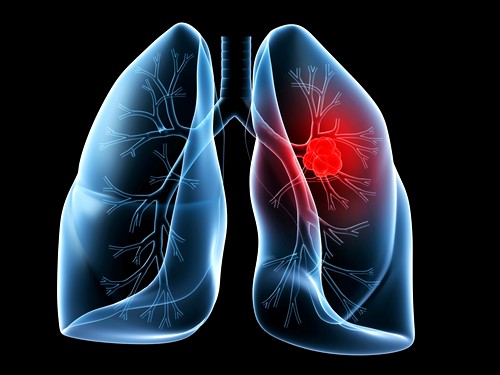

Рак легких может возникнуть в любой части легкого, но в 90-95% случаев опухолей образуется в эпителиальных клетках, выстилающих поверхность дыхательных путей (бронхов и бронхиол). По этой причине рак легких иногда называют бронхогенным раком, или бронхогенной карциномой. Опухоль развивается и на поверхности плевры (мезотелиома) и намного реже из других видов тканей, например, кровеносных сосудов.

Центральный рак лёгкого. Опухоль, происходящая из слизистой оболочки крупного бронха, проявляет себя довольно рано. При своём росте она раздражает слизистую оболочку бронха, вызывает нарушение бронхиальной проходимости и вентиляции сегмента, доли или всего лёгкого в виде гиповентиляции и ателектаза. В дальнейшем прорастая нервные стволы и плевру, опухоль вызывает болевой синдром и нарушение иннервации соответствующего нерва (диафрагмального, возвратного или блуждающего), а также картину вовлечения плевры в опухолевый процесс. Присоединяющееся метастазирование приводит к появлению вторичных симптомов со стороны поражённых органов и систем.

Периферический рак лёгкого. Периферическая опухоль в начальной стадии протекает бессимптомно ввиду отсутствия болевых окончаний в лёгочной ткани. В дальнейшем опухолевый узел увеличивается, прорастает бронхи, плевру и соседние органы; впоследствии в центре опухоли могут возникнуть распад и кровотечение.